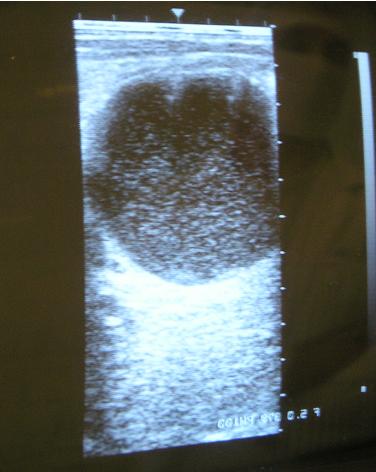

травма об руль велосипеда

То что на последней сонограмме, на мой взгляд - гной.

билому под узи пунктировали, получили ок 200 мл желтой, пенящейся полупрозрачной жидкости... адреналину было (когда первый шприц пошел)!!! тут же накрылись на лапаратомию (я уже не присутствовала - мчалась на другую работу) ... да уж, всё чудесатее и чудесатее (я про то, что когда желтое и прозрачное - это напрягает в плане эхинококка) ждем ответ

одним словом - никто ничего не понял, что это было. однозначно - не билома.

да, после пункции подозрение на эхинококк (кстати, девочка из эндемичного района) (хотя... во время пункции хирург отметил твердость капсулы, а слова, которые были произнесены при получении первой порции озвучить?....